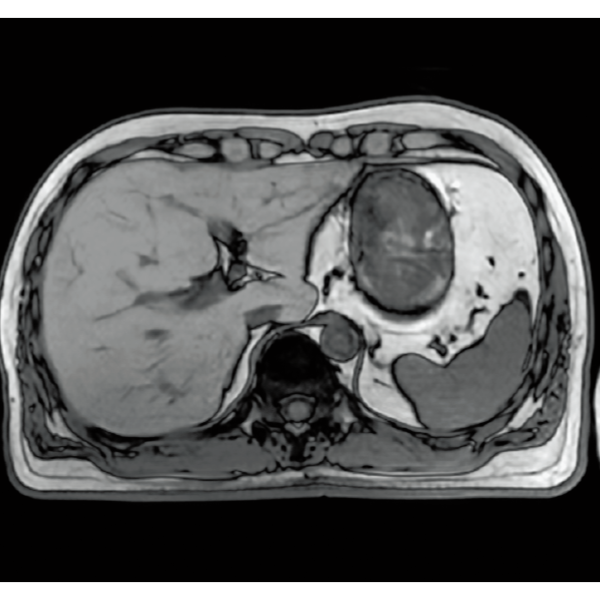

IP-RAPID×DLR Plusは撮像時間の短縮も可能なため、同一検査時間であれば、より多くの撮像が可能となります。従来検査に対して、異なる画像種類や断面など、追加撮像によって情報量を増やすことができ、診断をより確かなものに。

IP-RAPID×DLR Plusによって呼吸同期計測や横隔膜同期計測など時間のかかる検査を短くできます。さらに時間を短くし、息止めによる検査に変更することもでき、患者さまの状況に合わせて検査をお選びいただけます。選択肢が増えるので、検査の幅が広がります。

IP-RAPID×DLR PlusはVolumeScanやRadialScan、HalfScanといった基本撮像に加え、MultiContrastScanのFatSepやDWIなど多くの撮像法でお使いいただけます。広範囲DWIやWhole Spine撮像など時間のかかるWide Scanにも併用でき、多くの部位で従来よりも詳細な情報を得ることができます。

撮像データに生じたアーチファクトを除去・抑制したり、限られた撮像データから再構成画像を生成する機能を提供することで、再撮像率を低減し、スムーズなMRI検査の実現をサポートします。